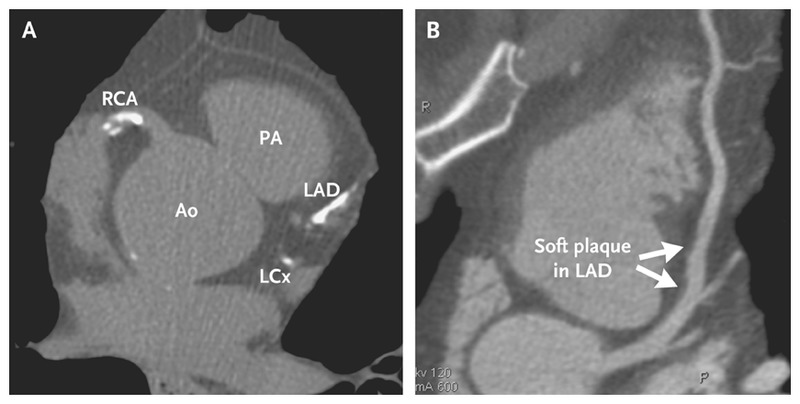

سی تی آنژیوگرافی قلب

سی تی آنژیو چیست؟

کلسیم اسکور- CAC Score - به چه معناست؟

رسوب کلسیم در عروق کرونر به چه معناست؟